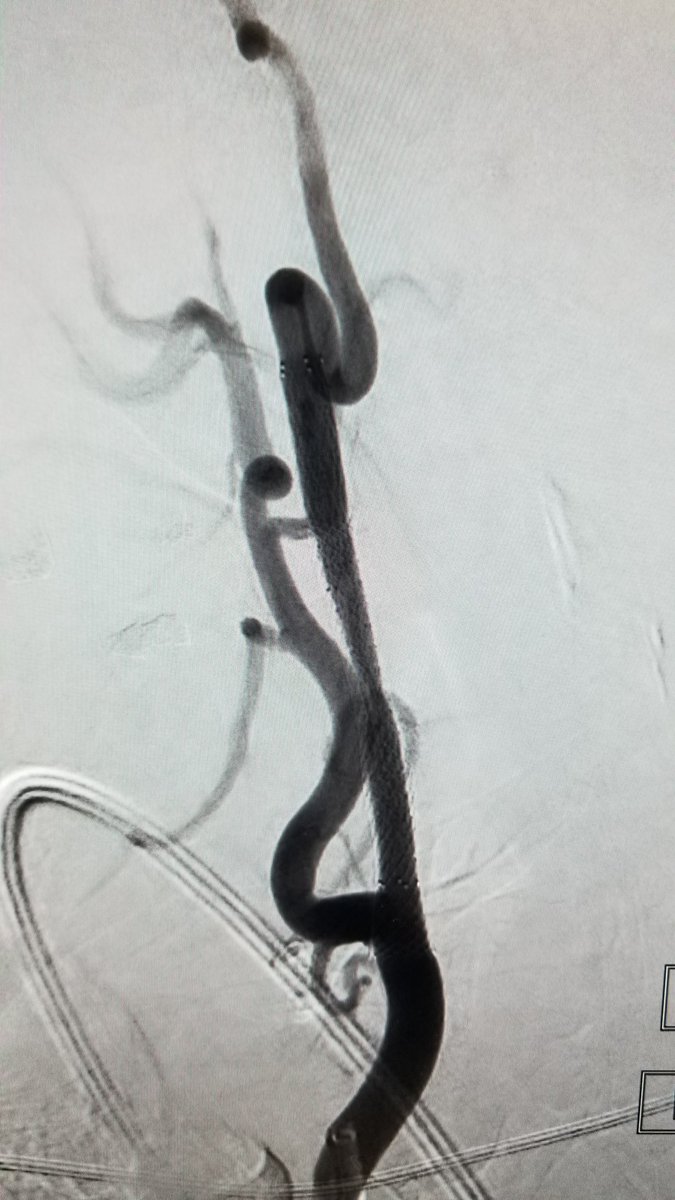

Record 5 #MT in 24 hrs last week. Great team effort including @Aggour @drpaulbhogal @hldmak. Highlight was this case performed by our trainee. Unable to shift this ICA T occlusion (3 stent passes) until we used a new #nimbus stent by @JNJMedDevices #innovation #LeaveNoELVOBehind

4

6

45